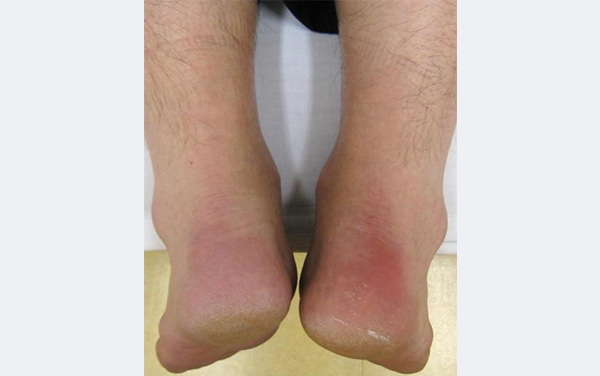

乾癬性関節炎かんせんせいかんせつえん 頭皮や全身に赤い発疹を伴う、関節の痛み - 古東整形外科・リウマチ科。